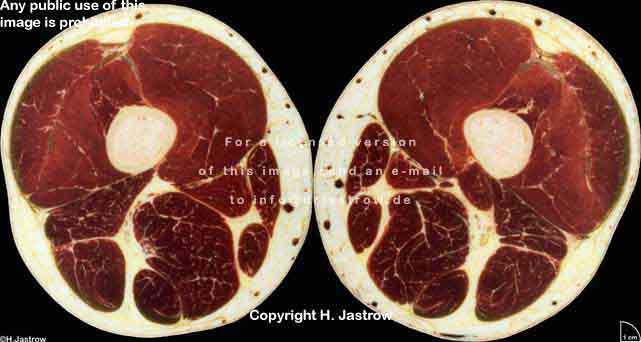

Visible Human male: Sectio transversalis 2201

NMR

Pd                          / T2 \                         T1